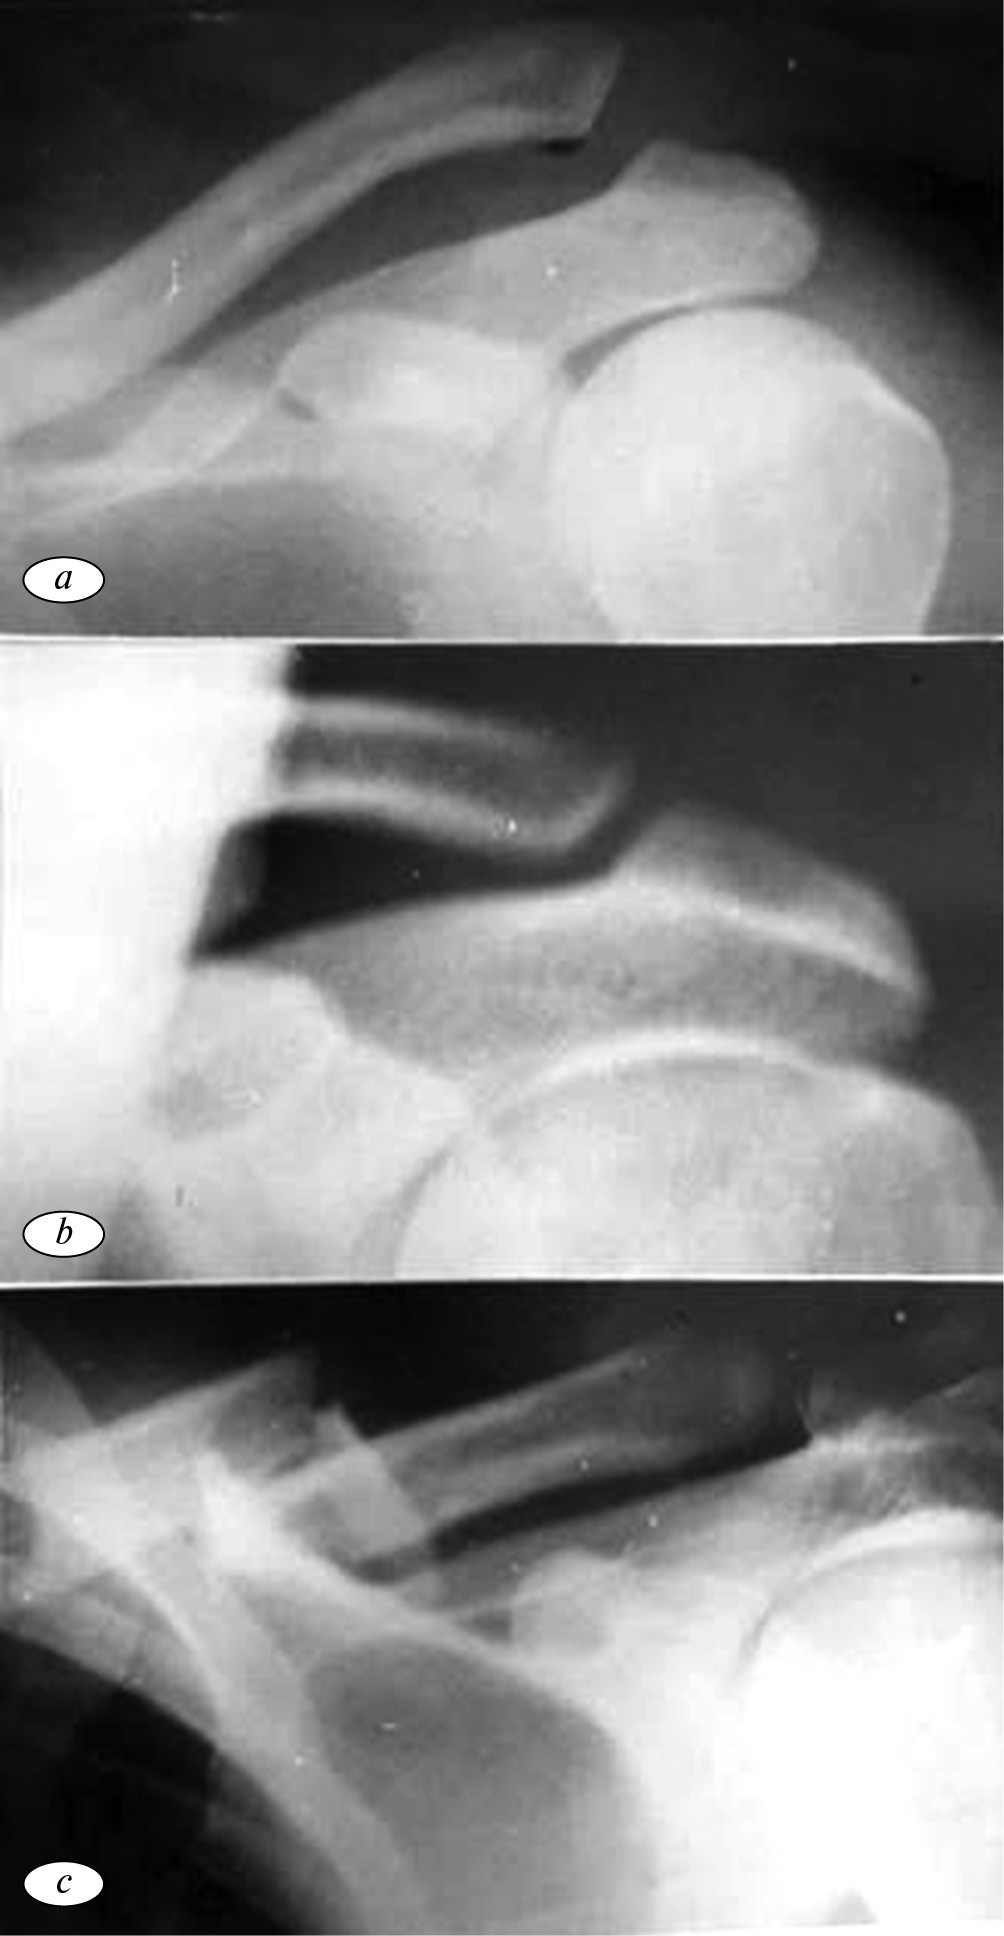

Как видно из таблицы, акромиальный вывих ключицы (62,0 %) возникал при наклонном расположении суставных поверхностей ключицы и акромиона (рис. 2, а, b).

Рис. 2. Рентгенограмма формы расположения суставных поверхностей ключицы и акромиона: а, b — при вывихах и после его вправления; c — при переломах ключицы

Fig. 2. X-ray diffraction pattern of the location of the articular surfaces of the clavicle and acromion: a, b — with dislocations and after reduction; с — with fractures of the clavicle

Это можно объяснить тем, что при непрямой травме, вследствие наклонного положения суставных поверхностей, ключица скользит по акромиону. При этом разрываются ключично-акромиальные связки, и ключица смещается кверху. Перелом ключицы чаще (78,0 %) возникал при вертикальном расположении суставных поверхностей аромиона и ключицы (рис. 2, с). Вследствие таких условий при непрямой травме суставная поверхность ключицы упирается в акромион. Воздействующая сила на ключицу осуществляется без напряжения связок, и в результате происходит ее перелом. Отмеченными нами особенностями отношения суставных поверхностей ключиц и акромиона можно объяснить чрезвычайную редкость подакромиальных вывихов ключицы.